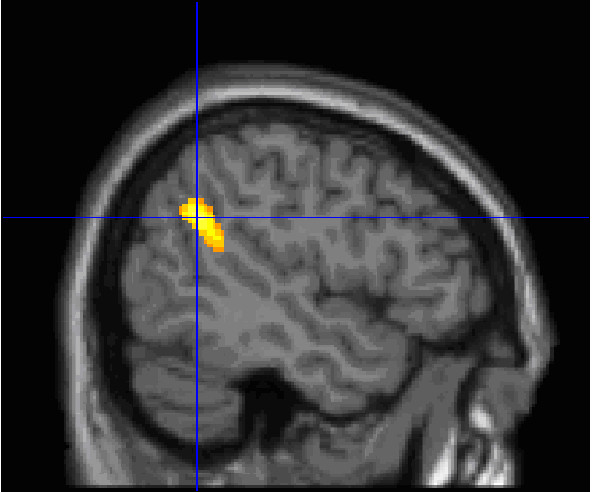

颞部顶骨连接部位(TPJ)(图片来源:Perrine Ruby/Inserm)

在这项新研究中,研究者团队想要找到区分强弱梦境回忆者的大脑部位。他们使用了正电子成像技术(PET)来测量41个志愿者分别在觉醒和睡眠状态下的自发性大脑活动。志愿者被划分为两组:21个“强梦境回忆者”,他们在每个星期平均记得5.2个梦;20个“弱梦境回忆者”,他们每星期平均只能回忆2个梦。强梦境回忆者,在无论是觉醒还是睡眠状态中,其内侧前额叶皮质(mPFC)和颞部顶骨连接部位(TPJ,与察知外界刺激相关的大脑部位)都显示出更强的大脑活动。